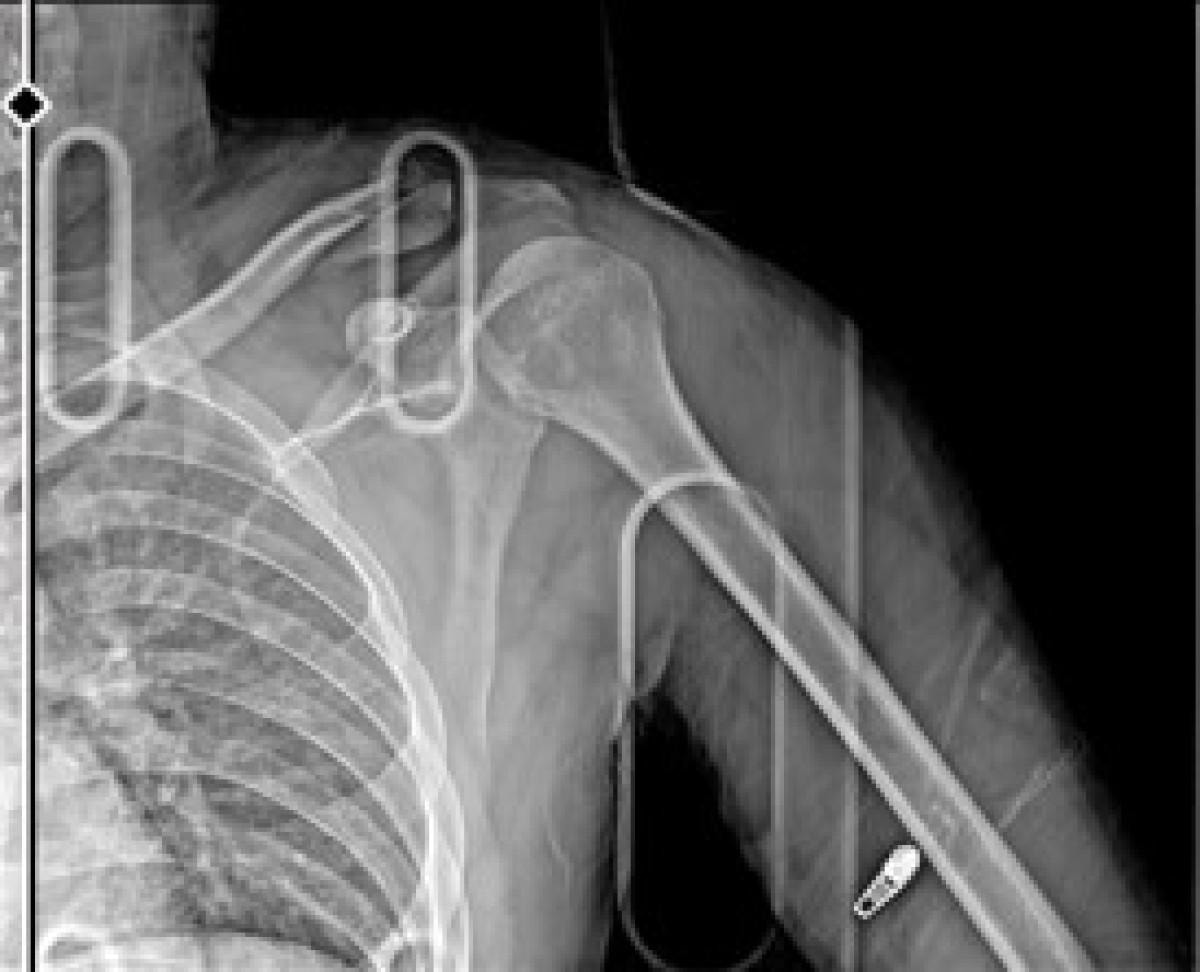

Çiçek, yaralı halde hastaneye kaldırılırken, sağ omzundan ameliyat oldu.

Çiçek'in platin takılan kolunda kalıcı hasar oluştu.

Şu an hala işlemler devam ediyor. Şu an koluma platin takıldı ve ömür boyu kalacak. İşimden oldum, motorum pert oldu. Motorum kullanılmayacak halde. O şekilde benim de 3-4 ay yatışım var. Sigortadan bir şey alamayacağım, benim çalıştığım yer buna müsait değil. Raporum hiçbir şekilde geçerli değil. Maddi ve manevi her açıdan beni zor duruma soktu ve hala rahat bir şekilde geziyor. Rahat bir şekilde paylaşımlar atıyor, görüyorum. Hiçbir şey yapılmıyor" dedi.